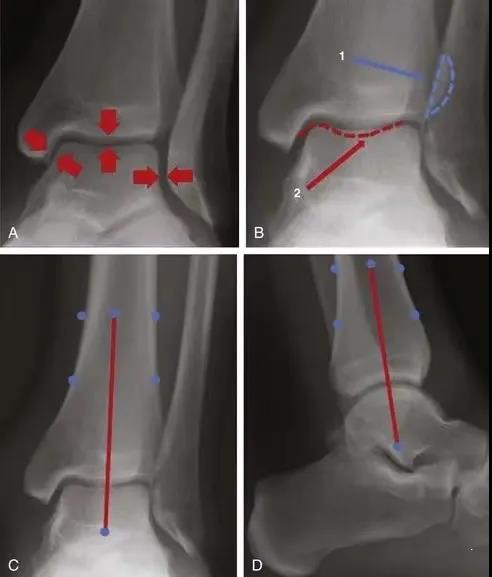

胫骨远端的关节面。注意与踝部的关节

A,关节面应在整个关节中等距(箭头)。B,腓骨与远端胫骨(1)和后踝(2)关节。C和D,正侧位腿的中轴(红线)穿过穹顶的中心和距骨。

对于术后片子,我们一定要进行评估,看看腓骨到底有没有解剖复位,距骨有没有外移,踝关节骨折很注重这点,pilon也不例外。

那篇著名的文献:距骨外移1mm,接触面积减少42%